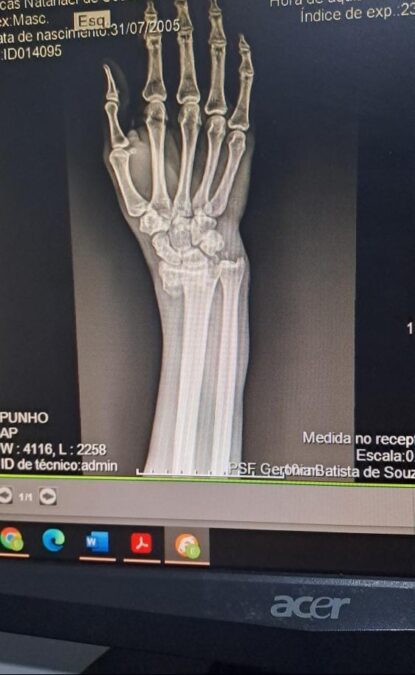

Segundo relato do jovem entregador, no último sábado, quando trabalhava fazendo entregas, ele passou próximo à antiga guarida, saída para Luziânia, quando cachorro grande entrou na frente de sua moto e o fez cair. Na queda, infelizmente, ele fraturou um dos pulsos.

Agora, o motociclista aguarda por uma cirurgia. Ele informou que além do cão em que ele colidiu, existiam outros quatro cães nas proximidades onde aconteceu o acidente.